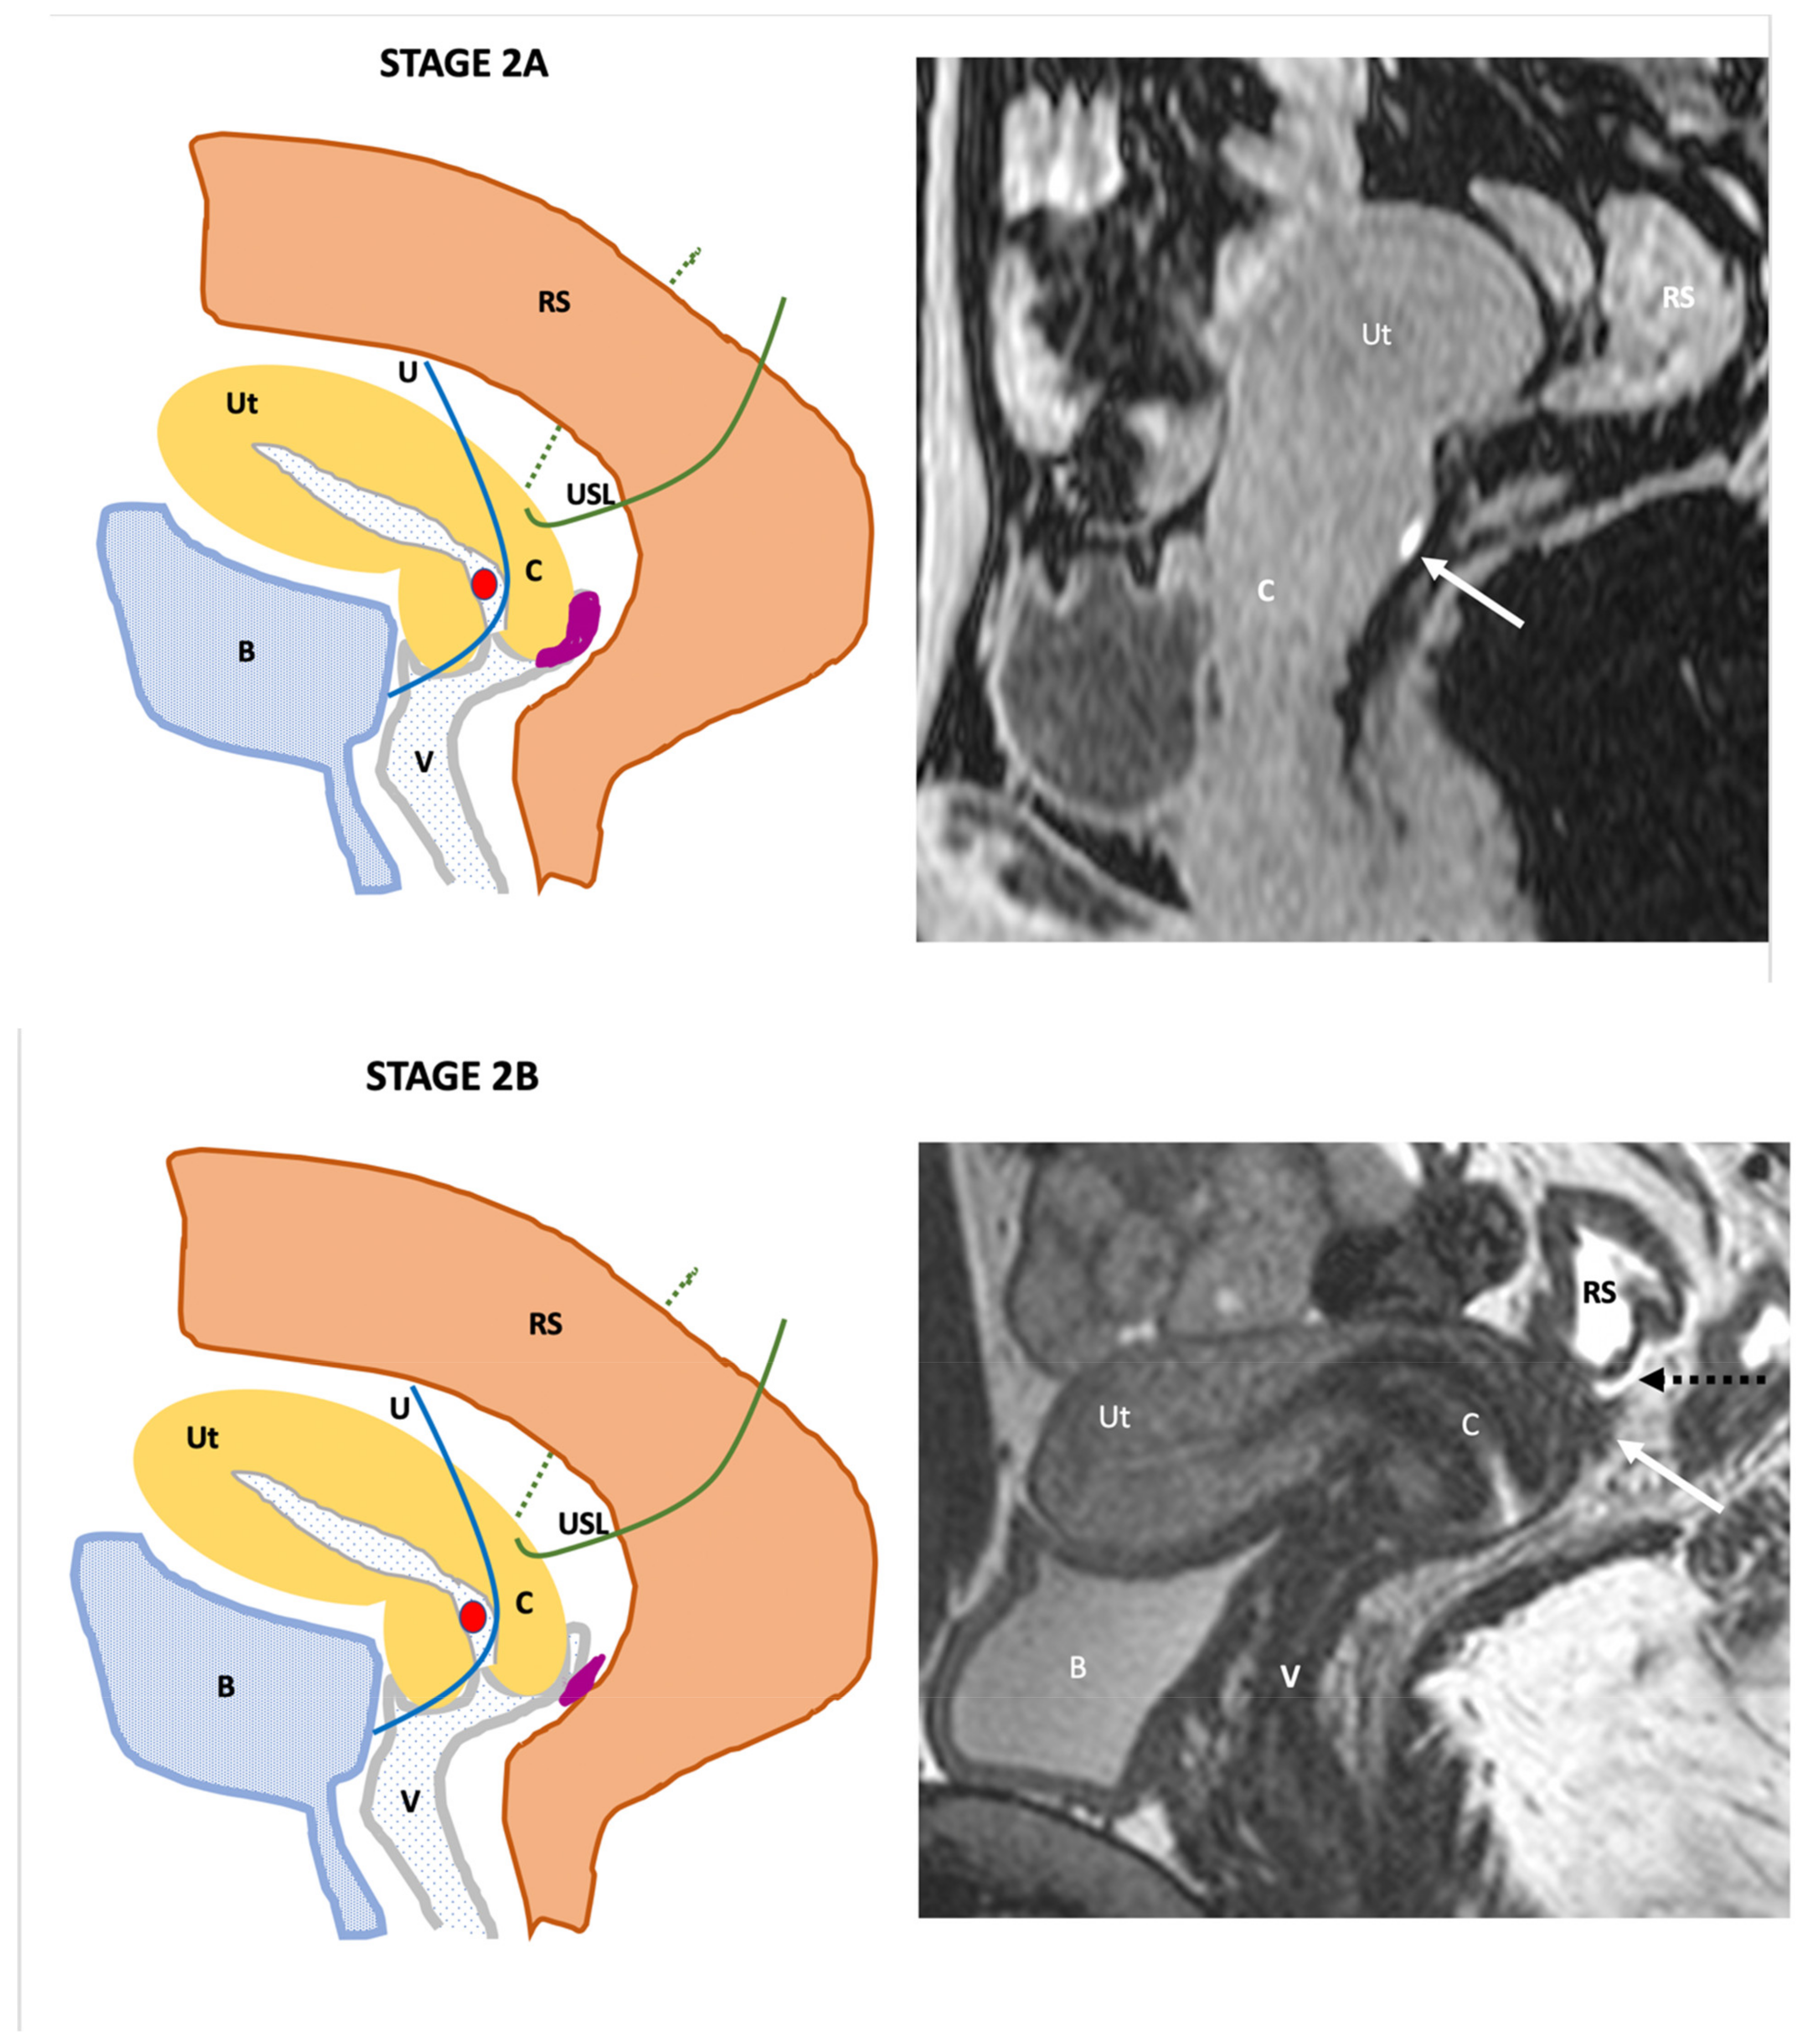

| Endo-Stage MRI II | Endometriosis invades beyond the retrocervical area, but not to the pelvic side-wall |

| |